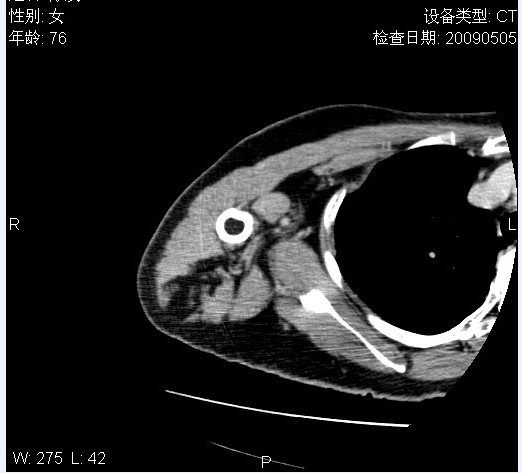

标题: CT19811:女,76岁,右上臂肿物1个月 [打印本页]

标题: CT19811:女,76岁,右上臂肿物1个月

使用了造影剂,可惜效果不太好

右肱骨上段软组织内见梭形低密度影,边界清楚,最长径约54mm.

病理结果:脂肪瘤。术中见肱骨骨膜受侵,有出血,量不详。

当时诊断意见:右肩三角肌内蔓状血管瘤(先天性动静脉瘘)。

本人对病理结果有个疑问:单纯的脂肪瘤内为什么有条状软组织影,那应该脂肪肉瘤才对啊?

该病例增强效果欠佳,由于经验欠缺,我们注射对比剂是由下肢足背静脉给药。注速2.0。虽然如此,但我们可以看到肿块内部条状软组织影是强化的,而且是连续的,并可见供血动脉是由腋动脉的其中一支即肩胛下动脉分出。从这些征象我们可以得出诊断:蔓状务血管瘤。

可病理偏偏为脂肪瘤,我怀疑取材有问题。因为蔓状血管瘤异常扩张的静脉外周是脂肪成分,它可以侵犯肌组织及骨骼。当取材于外周,那当然是脂肪瘤。此时我认为临床的最终诊断不应单从病理出发,应该综合考虑。